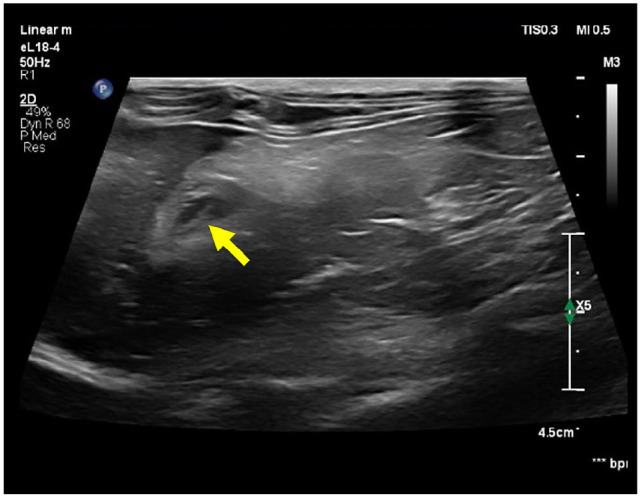

Case summary: A spayed female British Shorthair cat aged 1 year and weighing 2.6 kg presented with a 5-day history of vomiting and anorexia. Physical examination revealed icterus, and serum biochemistry showed markedly elevated bilirubin and liver enzyme levels. Abdominal ultrasonography revealed a dilated common bile duct (4 mm), mild gallbladder wall thickening and a round, hyperechoic foreign body located at the major duodenal papilla. A contrast-enhanced CT scan confirmed the presence of a 1.9 cm doughnut-shaped foreign body in the proximal descending duodenum, causing extramural compression of the common bile duct. Exploratory laparotomy and enterotomy were performed to remove the object. The cat recovered uneventfully, with normalisation of biliary parameters within 48 h and resolution of clinical signs by postoperative day 4.

Relevance and novel information: This case highlights a rare but surgically treatable cause of extrahepatic biliary obstruction (EHBO) in cats caused by a duodenal foreign body exerting extraluminal compression without intraluminal migration or mucosal invasion. It emphasises the value of cross-sectional imaging and timely surgical intervention in achieving favourable outcomes. To the authors' knowledge, this is the first peer-reviewed report of feline EHBO caused by extramural duodenal compression that was successfully resolved without biliary tract incision.